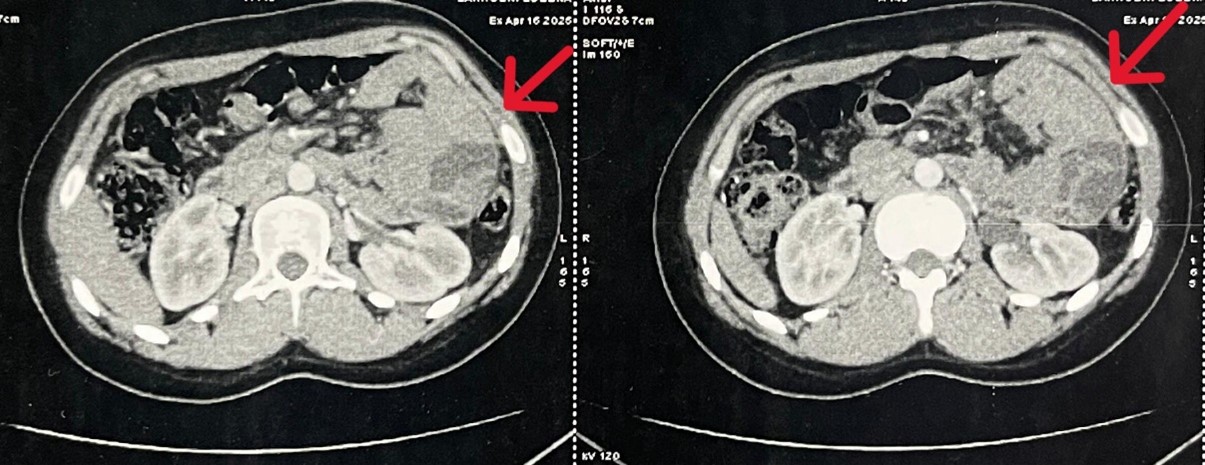

An abdominal computed tomography scan, performed initially prior to presentation at the emergency department, showed a thin layer of intraperitoneal fluid, clustering of small bowel loops in the left hypochondrium, mesenteric hyperemia, and anterior displacement of the inferior mesenteric vein trunk. These findings were suggestive of a left paraduodenal hernia.

Figure 1: Computed tomography image demonstrating a left paraduodenal hernia.

Typical CT findings include:

- Clustered small bowel loops forming a sac-like mass in the left upper quadrant

- Location posterior to the stomach and pancreas or anterior to the left kidney

- Displacement and engorgement of mesenteric vessels

- Inferior mesenteric vein forming the anterior border of the hernia orifice

These features are consistently described across multiple reports and case series [7,12].